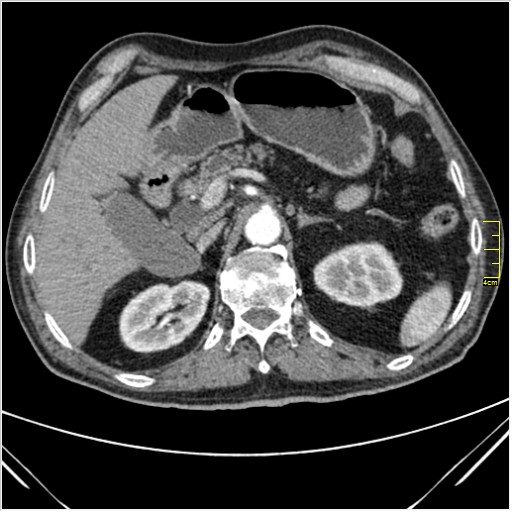

Мужчина 62 года с желтухой

Опухоль головки поджелудочной железы, расширение холедоха и панкреат. протока (Double Channel sign)

Карциномы панкреас гиподенсны на КТ с болюсом, т.к. содержать много соединительной и фиброзной ткани, в отличие от нормальной ткани железы, которая (как любая железа) хорошо васкуляризирована. Поэтому если видим в панкреас солидное гиподенсное образование - всегда настораживает на предмет рака. Второй момент: обязательная оценка взаимоотношения опухоли к ВБА и ВБВ, на предмет оценки операбельности.